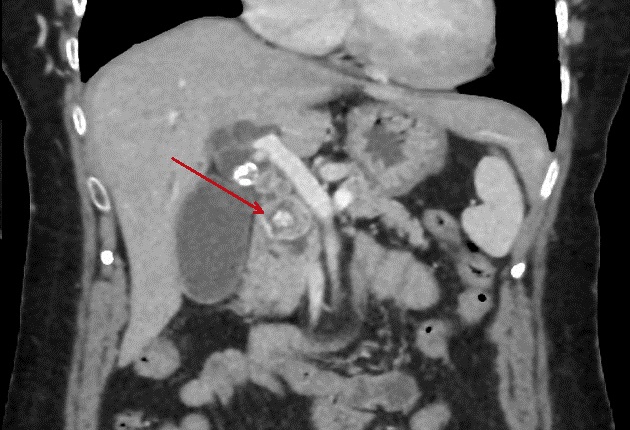

Meme cas en coupe coronal (

frontal ) . Calcul choledocienne ( fleche rouge ) .

Voies biliaires intra hepatiques sont en legerement

dilate .. |